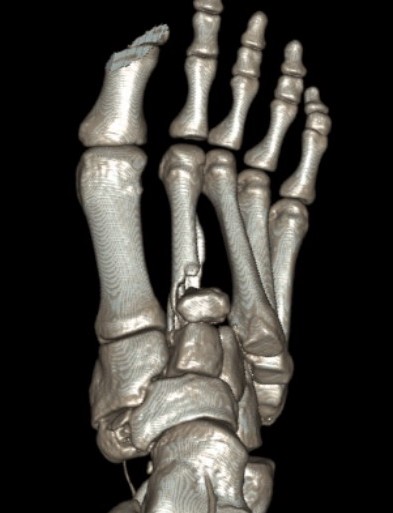

CT scan

Dorsal displacement of metatarsals

Compression fractures / nutcracker of cuboid

1. Diastasis of the intermetatarsal gap between the 1st and 2nd metatarsals

2. Widening of the space between the medial cuneiform and base of 2nd metatarsal

3. Second metatarsal Fleck sign - avulsion of Lisfranc ligament from base of 2nd metatarsal

4. Widening of inter-cuneiform distance

5. Dorsal subluxation of the metatarsals